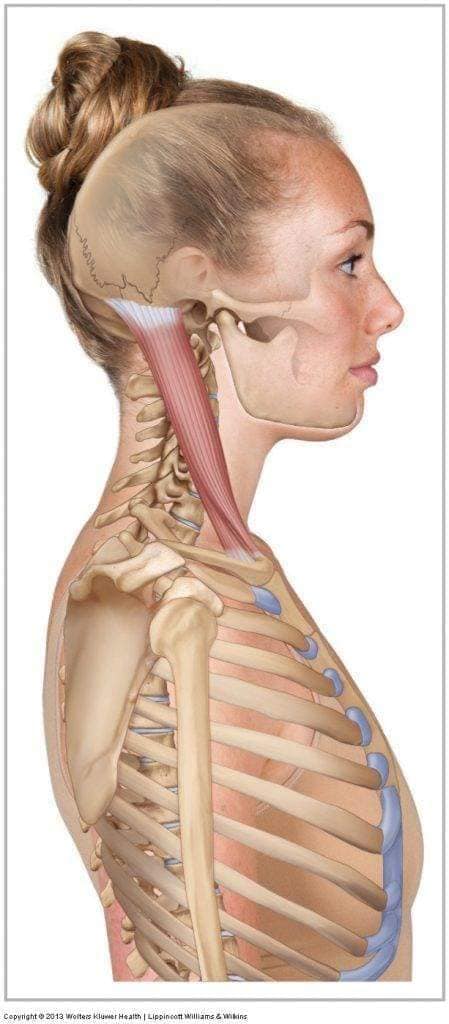

Шийні м'язи

Шийні м'язи мають важливе значення для підтримки голови і забезпечення її рухів.

М'язи, що згинають шию: М'язи, що згинають голову (м'язи передньої групи): виконують рухи, які дозволяють опускати і піднімати голову.

М'язи бічної групи

М'язи, що повертають голову: Стерноклейдомастоїдний м'яз: один з найважливіших м'язів, який дозволяє здійснювати повороти і нахили голови. Він походить від грудини та ключиці і прикріплюється до соскоподібного відростка скроневої кістки.

М'язи задньої групи

М'язи, що розширюють шию: М'язи, що розширюють шию: включають трапецієподібний м'яз, який бере участь у піднятті плечей і розширенні шиї.